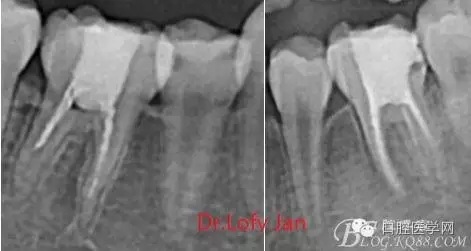

前言:自己做的一些曲面斷層片在未試尖根管治療中的病例整理,發(fā)現(xiàn)問題很多包括自身的,技術(shù)的,還有設(shè)備的問題,予以總結(jié)整理并期待進(jìn)一步提高。

根管治療術(shù)是牙體牙髓疾病治療中最復(fù)雜和最關(guān)鍵的治療項目。根管充填材料抵達(dá)根尖、并能嚴(yán)密堵塞根尖孔,是確保根管治療效果的關(guān)鍵指標(biāo)。為了保證根管充填到位,醫(yī)生需要在術(shù)前照牙片以了解牙根根管的數(shù)量、彎曲程度和長度,在術(shù)中有時需要插針照牙片來精確測量根管長度,術(shù)后必須照牙片以確定是否根管充填到位,如果欠填或超填,就需要重新充填、重新照牙片確認(rèn),直到根管充填到位。所以,在患者接受根管治療時有時會反復(fù)照牙片。

病例分析:曲面斷層片在x線輔助診斷與檢查中目前大多數(shù)文獻(xiàn)和著作都建議只能作為初診拍片檢查手段,不能作為終末疾病的確診與手術(shù)療效的評價指標(biāo),臨床大部分中小型門診都因為設(shè)備不齊全導(dǎo)致信息偏差很大。